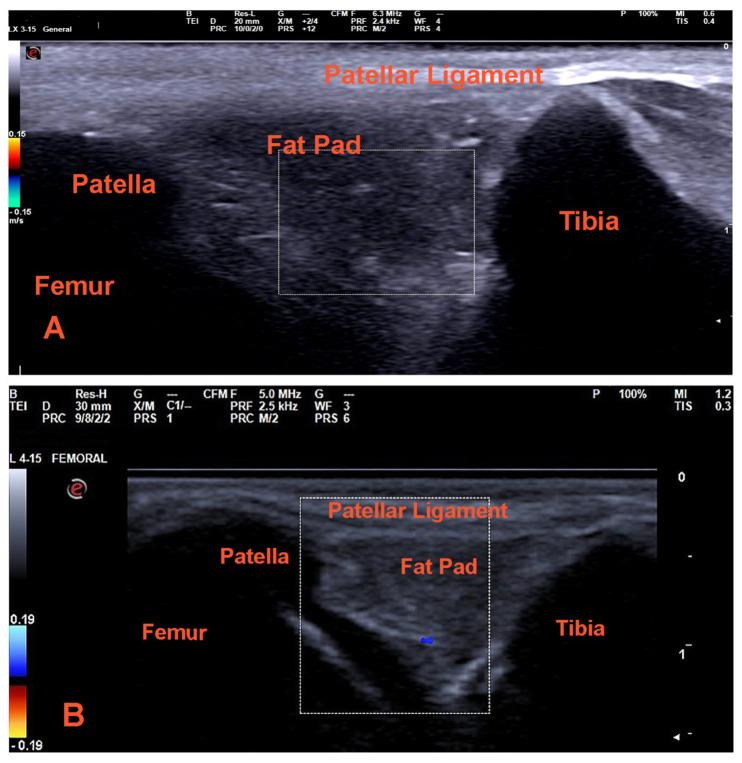

This review presents a comprehensive overview of various ultrasound imaging techniques employed in the evaluation of the canine knee joint. It critically analyzes studies conducted on both human and animal subjects, with a focus on the diagnostic accuracy of B-mode ultrasound, Doppler examination, contrast-enhanced ultrasound, and elastography in both normal and pathological conditions. The review underscores the necessity of strict adherence to the protocols of each ultrasound modality and emphasizes the importance of a thorough understanding of the anatomical region to achieve optimal outcomes. The findings suggest that these ultrasound techniques can significantly enhance the diagnostic process, providing valuable insights into anatomy, size, blood supply, and tissue elasticity. Additionally, in cases where advanced imaging modalities such as computed tomography (CT) or magnetic resonance imaging (MRI) are cost-prohibitive or less accessible, ultrasound serves as a reliable alternative, delivering high diagnostic accuracy and critical information regarding mechanical changes in the joint and neovascularization.

本综述全面概述了用于评估犬膝关节的各种超声成像技术。它批判性地分析了针对人类和动物受试者进行的研究,重点关注B型超声、多普勒检查、超声造影和弹性成像在正常和病理情况下的诊断准确性。该综述强调了严格遵守每种超声模式协议的必要性,并强调了深入了解解剖区域以获得最佳结果的重要性。研究结果表明,这些超声技术可以显著增强诊断过程,为解剖结构、大小、血液供应和组织弹性提供有价值的见解。此外,在计算机断层扫描(CT)或磁共振成像(MRI)等先进成像模式成本过高或难以获得的情况下,超声是一种可靠的替代方法,可提供关于关节机械变化和新生血管形成的高诊断准确性和关键信息。